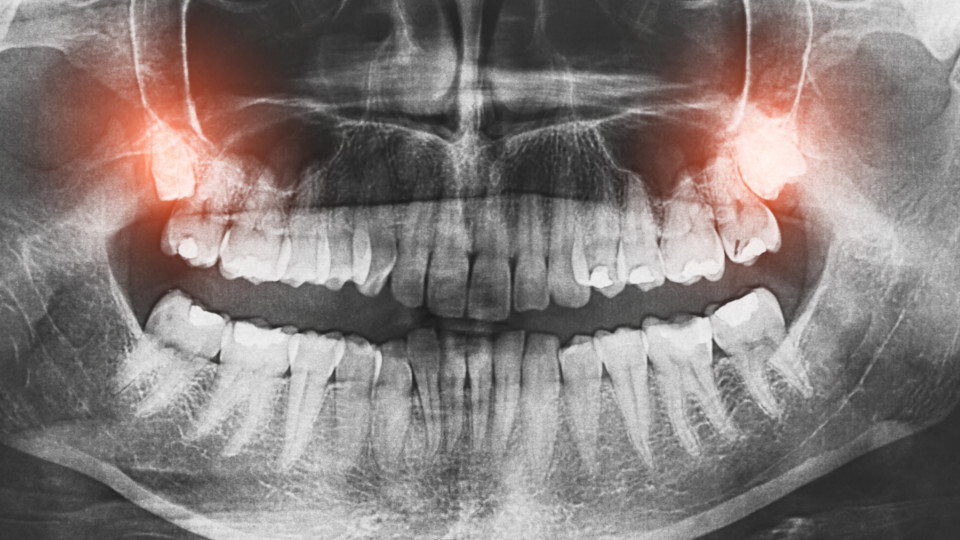

Eine gute Vorbereitung und eine sorgfältige Nachsorge unterstützen den Behandlungserfolg und fördern die Heilung nach einem oralchirurgischen Eingriff. Patientinnen und Patienten können durch einfache Maßnahmen selbst viel dazu beitragen, Komplikationen zu vermeiden und sich schneller zu erholen.

Dieser Beitrag gibt einen kompakten Überblick über die wichtigsten Schritte vor und nach größeren zahnchirurgischen Behandlungen.